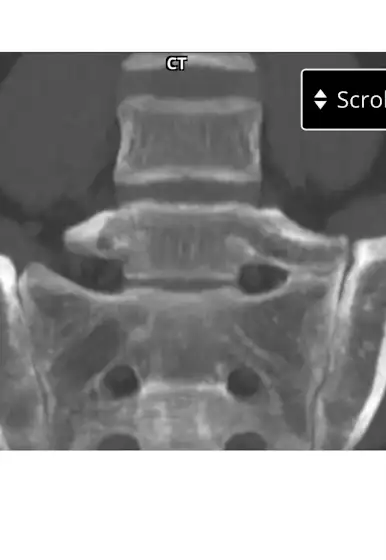

Decided to post this if people wonder what I talk about when I say i have a extra connected bone